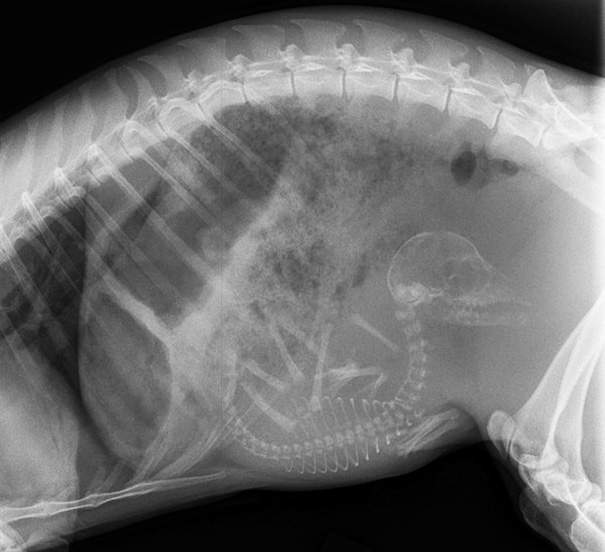

原汁原味的內容在這裡▼貓媽媽的大肚子裡裝了這麼多小貓唷!

圖片來自:boredpanda